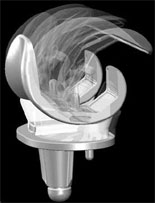

PROTESI POLSO E MANO

Accoppiamenti articolari con polietilene ad alta resistenza usura; ceramica delta e metallo metallo.

Modularità per ottenere una riscostruzione anatomica.